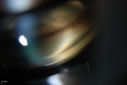

Silicone Oil Bubbles in the Angle1273 viewsPatient is evaluated for glaucoma associated with ocular inflammation. VA is CF in the right eye and 20/50, left eye. Gonioscopy photos shows little silicone oil bubbles in the inferior angle of the right eye. Patient to consider removal of silicone oil. 55555

(1 votes)